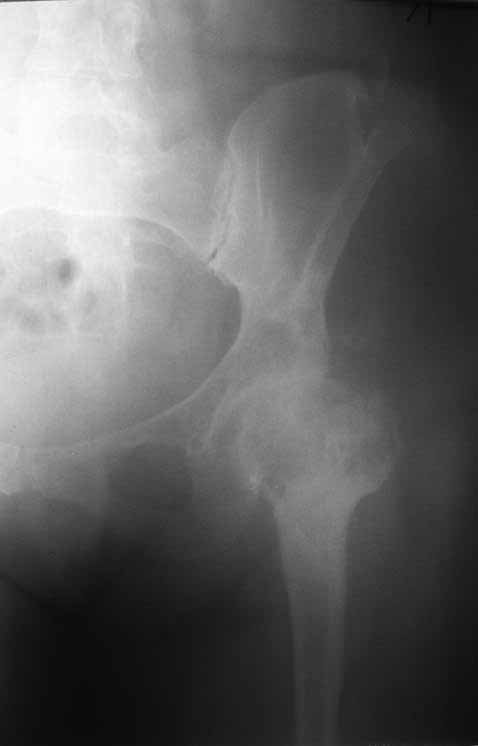

Пациентка 45 лет. Бесцементное эндопротезирование левого тазобедренного сустава 6 лет назад (впадина RM, Mathys, металл-металл, ножка Зульцеровская). За 10 лет до протезирования – коррегирующая остеотомия бедренной кости, которая не срослась в течение года до удаления пластины, а затем срослась в течение 3 месяцев иммобилизации в кокситной повязке. После протезирования получилось наблюдать пациентку почти постоянно, поскольку через 2 года синтезировал ей лодыжки на оперированной стороне, затем, через несколько месяцев удалил фиксаторы, а в 2009г. резецировал мениск на противоположной стороне. Боли все эти годы не беспокоили. Пациентка чуть выше среднего роста, вес тела нормальный. Физические нагрузки переносила хорошо. Работает на 7 этаже без лифта. Год назад экстирпация матки по поводу лейомиомы больших размеров. Несколько месяцев назад появились боли в области левого тазобедренного сустава. При рентгеновском и КТ исследованиях (июль с.г.) – нестабильность тазового компонента. От предложенной замены протеза пациентка на тот момент, слава богу, отказалась. Через какое то время боли в области левого тазобедренного сустава практически полностью прошли, а около 2 месяцев назад появилось ощущение патологической подвижности таза и боли в паху справа, которые через некоторое время уменьшились, а потом снова усилились после значительных физических нагрузок (много ходила по песку на пляже, носила тяжести). Ежедневно принимала диклофенак. На рентгенограммах – переломы правой лонной кости. Сейчас госпитализирована из-за болей в паху справа. Боли слева не беспокоят. На фоне снижения нагрузок в стационаре боли значимо уменьшились. Способна ходить без средств дополнительной опоры.

На представленных снимках тазобедренный сустав до и сразу после операции, затем 2 снимка 2009г., когда ничего не беспокоило, затем КТ 2-х месячной давности и вчерашние рентгенограммы обоих тазобедренных суставов.